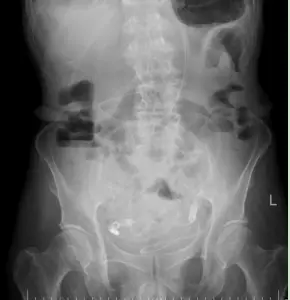

导管开始工作后,积聚的肠内容物被持续引出,腹胀腹痛的症状一天天缓解。老人的肠道功能慢慢恢复,复查腹平片显示梗阻情况明显好转。在护理团队的精心照料下,老人从卧床不起到能下地活动,从禁食禁水到逐渐恢复饮食,一天天好起来。2月24日,王大爷顺利出院,重新回归了正常生活。